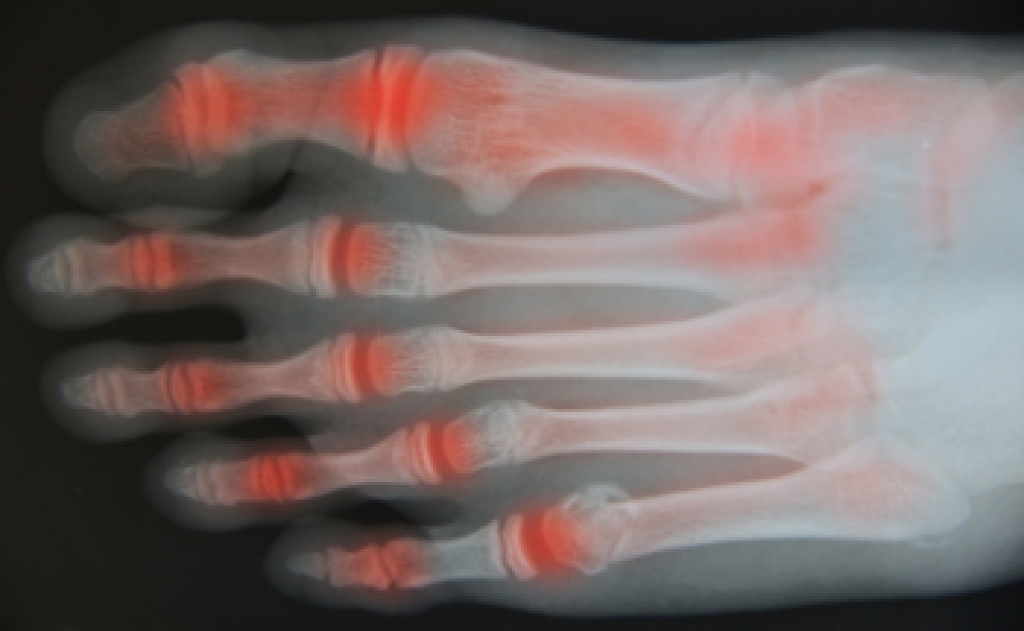

Rheumatoid Arthritis May Affect Different Parts of the Foot

If you are experiencing chronic pain, which may be caused by inflammation in your feet, you may have rheumatoid arthritis. This uncomfortable ailment is caused by an autoimmune condition and will typically affect the tissues in the feet, which may cause severe pain and swelling. When this condition develops in the feet, the joints in the ankle may become affected as a result of possible damage that the tissues and ligaments may endure. This may cause diminished support in the ankle bones and can cause difficulty in walking. If rheumatoid arthritis (RA) develops in the center of the foot, damage to the ligaments may cause the arch to gradually collapse, and desired relief may be felt by wearing shoe inserts. If you are experiencing this type of foot pain, it’s suggested to consult with a podiatrist, so the proper treatment techniques can begin.

Rheumatoid Arthritis (RA) is an autoimmune disorder in which the body’s own immune system attacks the membranes surrounding the joints. Inflammation of the lining and eventually the destruction of the joint’s cartilage and bone occur, causing severe pain and immobility.

Rheumatoid Arthritis of the Feet

Although RA usually attacks multiple bones and joints throughout the entire body, almost 90 percent of cases result in pain in the foot or ankle area.